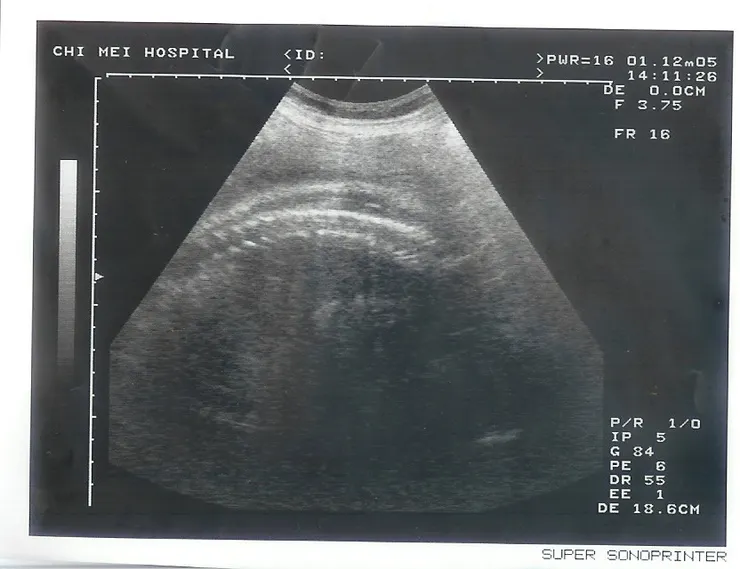

照超音波的時候,醫生先摸一摸我的肚子,還壓一壓,不知在檢查什麼?我問醫生,我現在子宮收縮,到底可不可以做產前運動?醫生說最好不要,還是等36週以後再多走動。

我自言自語說:「不知胎位正不正?」

醫生說:「看一下就知道,是正的。差不多2公斤。」

我對著螢幕說:「這個不是頭圍?」

醫生說:「不是咧,這是腹部咧。」

我指著螢幕左邊說:「我說的是這張。」

醫生說:「對啦!既然這樣,我秀嬰兒的脊椎給妳看好了!」

秀完,醫生就印出一張小咪脊椎的超音波照給我,呵呵。